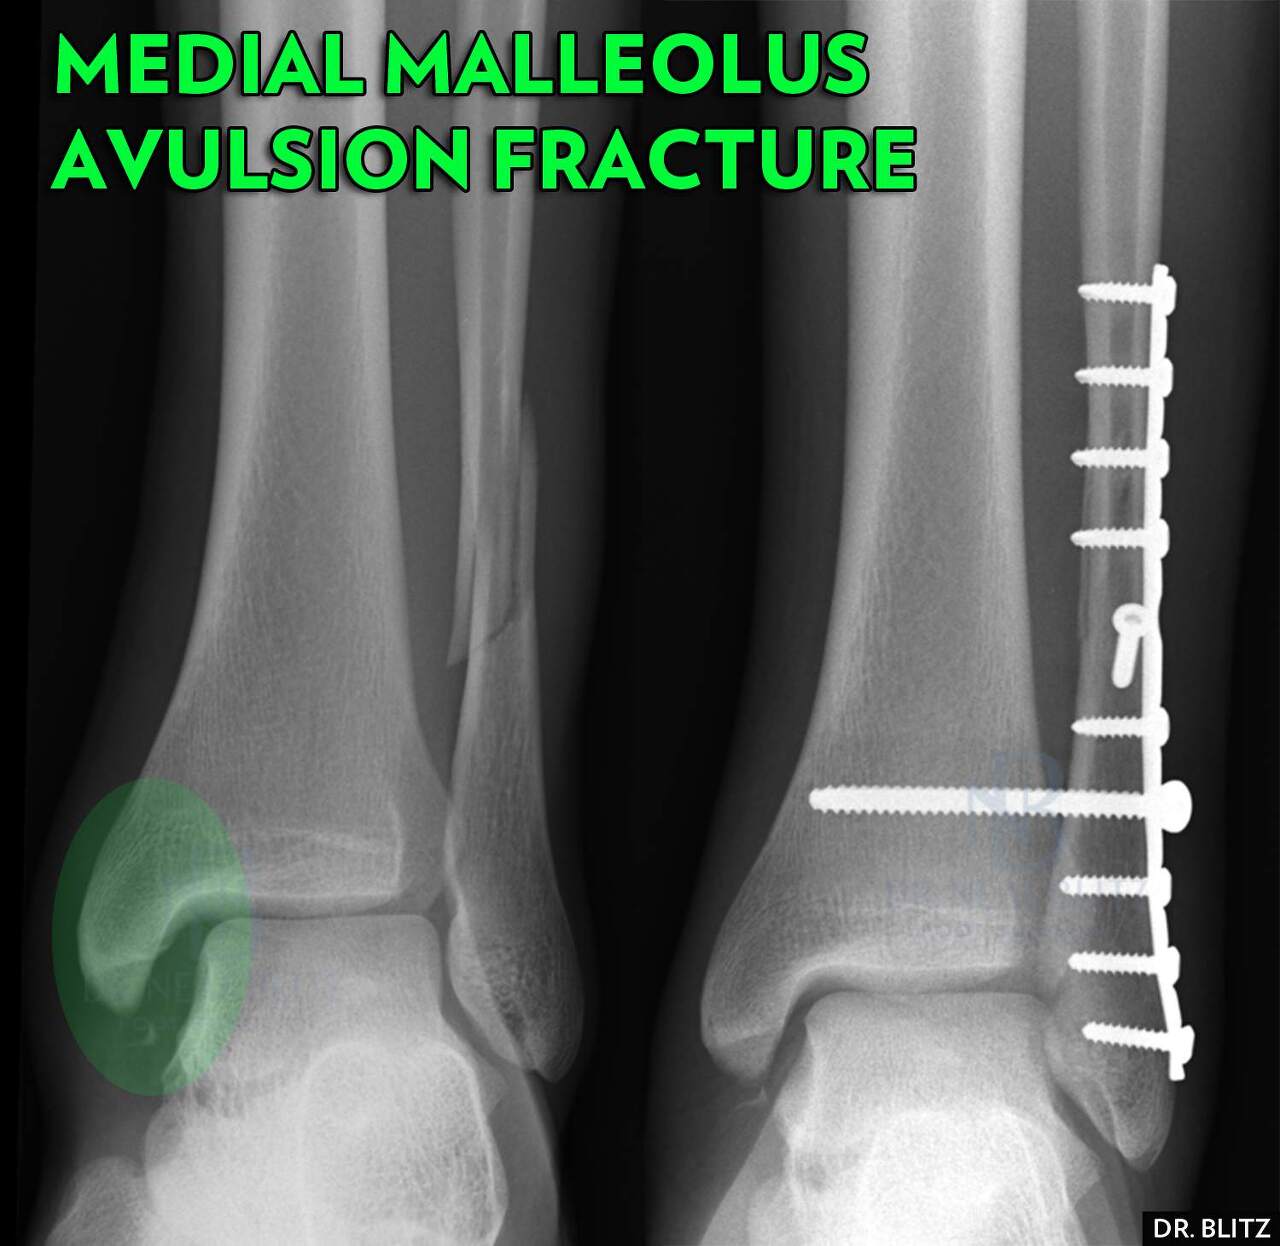

4) 삼각인대

내측 삼각인대는 3개 층으로 구성. 완전 파열은 거의 없음.

기타 골절 수술